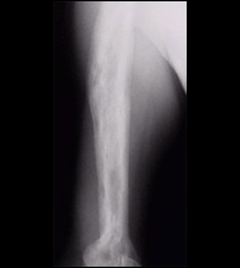

Humerus

Figure 5: Paget's disease of the humerus. Note how dense and wide the bone is. It is also patchy from areas of active bone turnover.

Paget’s disease of the humerus. The bone is dense, wide, and patchy, whereas the active bone is turning over.